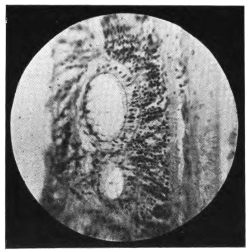

PLATE III.

16.

ABUNDANT EXUDATE INTO VITREOUS CAVITY

curly bracket span

42

17.

LENS FIRMLY FIXED BY ORGANIZED EXUDATE

18.

LENS FIRMLY FIXED BY ORGANIZED EXUDATE, BUT IN UNUSUAL POSITION

19.

TOTAL DETACHMENT OF RETINA, WITH CYST FORMATION

20.

RECLINED LENS LYING IN FRONT OF THE HYALOID BODY

21.

RECLINED LENS LYING IN FRONT OF THE HYALOID BODYxii